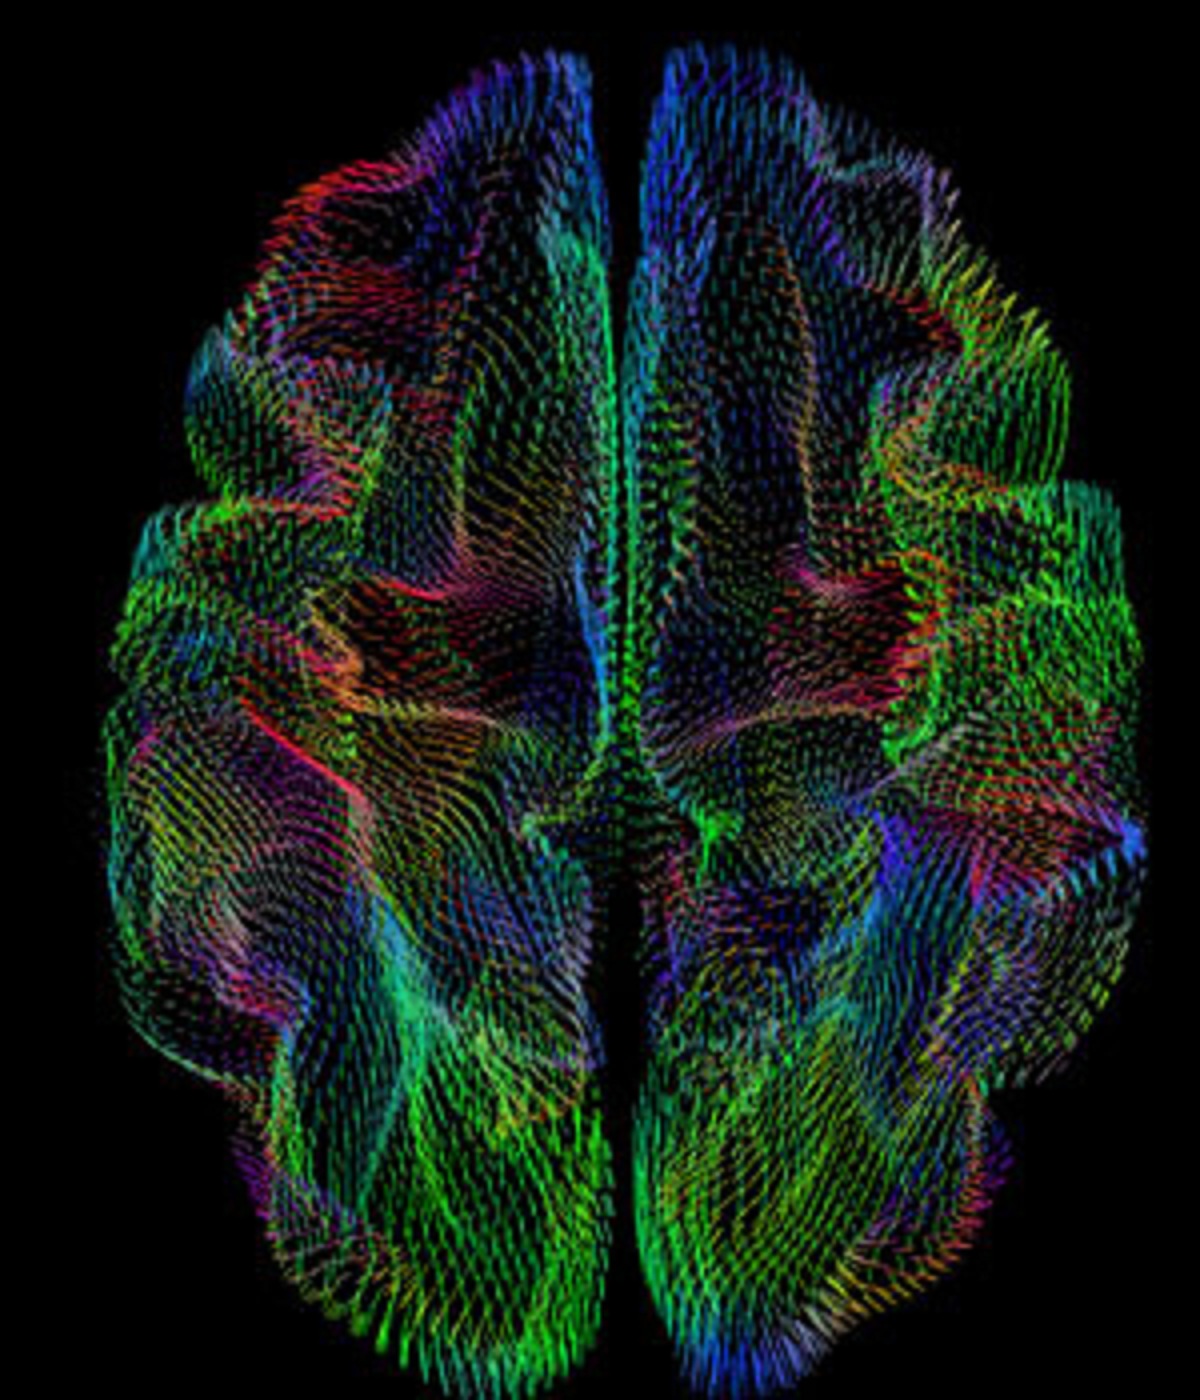

La forma de la corteza cerebral está correlacionada con la ascendencia genética. Fuente: UC San Diego.

Investigadores de la Universidad de California en San Diego (EE.UU.) han descubierto que la forma tridimensional de la corteza cerebral -la capa exterior arrugada del cerebro que controla muchas funciones del pensamiento y las sensaciones- está fuertemente correlacionada con la herencia ancestral.

"Había varias diferencias sistemáticas, sobre todo en los patrones de plegado y girificación de la corteza", dice Jernigan, también director del Centro para el Desarrollo Humano de la universidad. "Esos patrones eran un reflejo bastante fuerte de la ascendencia genética."

Los investigadores informaron de que los patrones corticales representaron entre el 47 y el 66 por ciento de la variación entre la ascendencia genética de los individuos, dependiendo del linaje ancestral.